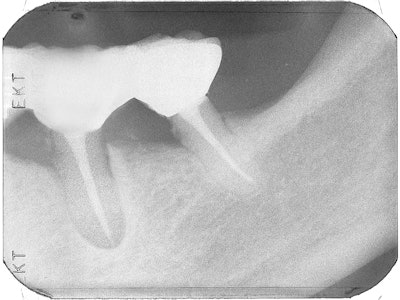

This patient had a periapical lesion around his lower left second bicuspid and the mesial root of his first molar (Nos. 19 and 20). The mesial root of the molar was decayed, but the distal root was in good condition. I decided to perform root canal therapy, hemisect the molar and remove the mesial root, obturate the canals with Pulpdent Root Canal Sealer, and see if I could stimulate healing of the periapical lesion. If the treatment failed, extraction could be performed at a later date.

This case predates Heithersay's 1975 research in the Journal of the British Endodontic Society that led to our knowledge of the use of Pulpdent paste for healing periapical lesions, although we now know that treating with calcium hydroxide first will produce the highest success rate.

I had seen periapical healing after obturating canals with Pulpdent Root Canal Sealer and was willing to give it a try. The small extrusion of sealer past the apex is not a concern, but, in any event, the material is biocompatible and usually resorbs over time.

In this case, healing occurred, and a radiograph taken five months later shows resorption of the extruded sealer and healing of the periapical lesion.

A radiograph taken 4.5 years later shows the completed case with bridge in place, bone fill, and the healed periapical lesion.